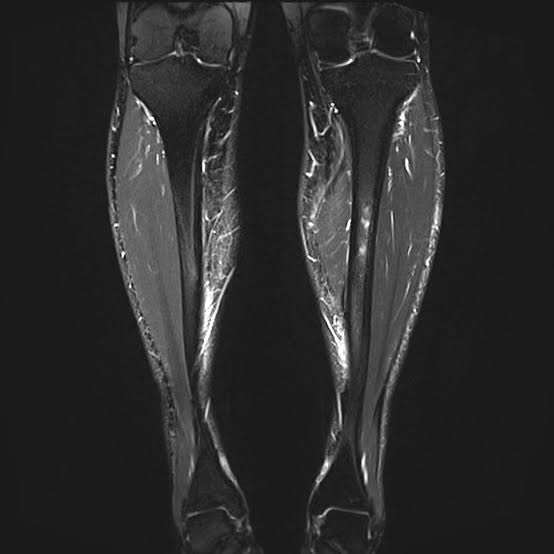

From e3rehab.com